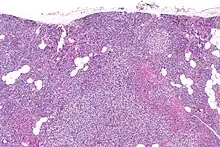

Primary hyperplasia of the parathyroid gland, results from both hypocalcaemia and increased phosphate levels by decreasing expression of calcium sensing receptors and vitamin D receptors at the parathyroid gland.[8][4] These decreases in receptor expression lead to hyperfunctioning of the parathyroid. Hyperfunction of the parathyroid gland is thought to exacerbate primary hyperplasia which evolves further to a secondary more aggressive hyperplasia. Histologically, these hyperplasic glands can be either diffuse or nodular.[24] Primary hyperplasia, usually resulting in diffuse polyclonal growth is manly related to reversible secondary hyperparathyroidism. Secondary hyperplasia of the parathyroid gland is more often a nodular, monoclonal growth that sustains secondary hyperparathyroidism and is the catalyst in the progression to tertiary hyperparathyroidism. Nodular hyperplastic glands in tertiary hyperparathyroidism are distinctly larger in both absolute size and weight up to 20-40-fold increases have been reported.[25][26][24]

Parathyroid glands are normally composed of chief cells, adipocytes and scattered oxyphil cells.[27][14] Chief cells are thought to be responsible for the production, storage and secretion of parathyroid hormone. These cells appear light and dark with a prominent Golgi body and endoplasmic reticulum. In electron micrographs, secretory vesicles can be seen in and around the Golgi and at the cell membrane. These cells also contain prominent cytoplasmic adipose.[27][14] Upon onset of hyperplasia these cells are described as having a nodular pattern with enlargement of protein synthesis machinery such as the endoplasmic reticulum and Golgi. Increased secretory vesicles are seen and decreased intercellular fat is characteristic.[27][24] Oxyphil cells also appear hyperplasic however, these cells are much less prominent.